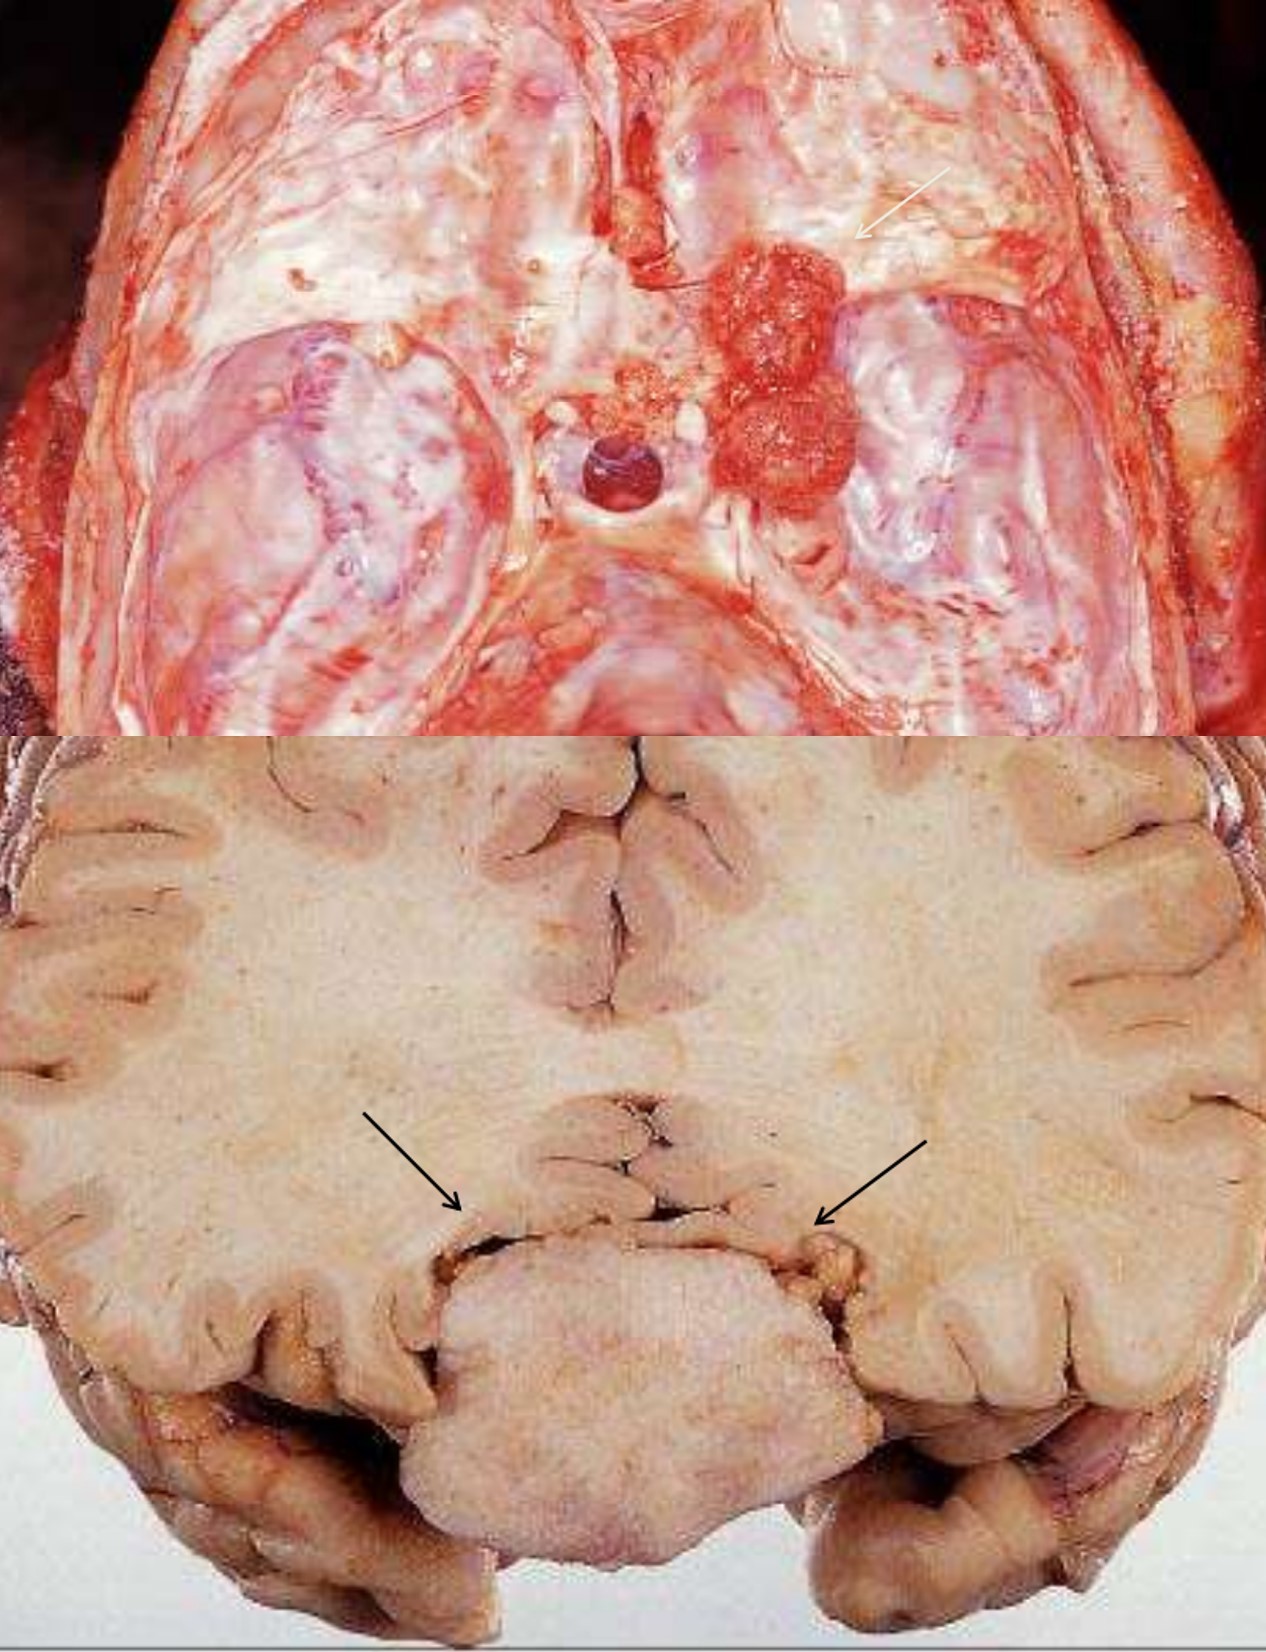

Meningioma

Meningioma Grades and subtypes